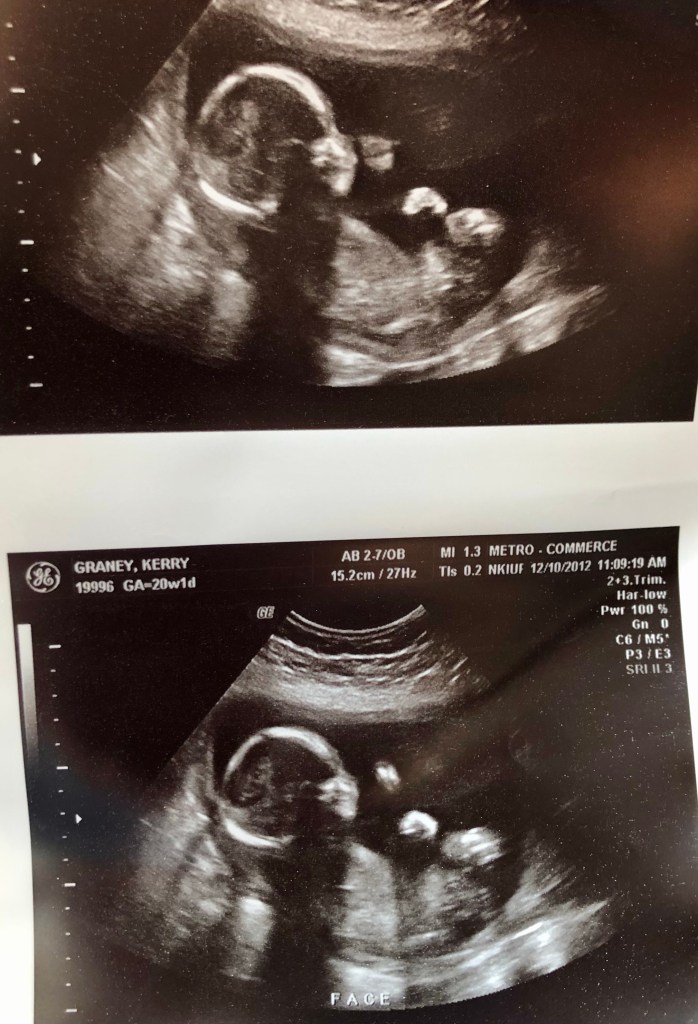

If you’ve ever had a baby, you know that the twenty week ultrasound is a big deal! It is also called the anatomy scan. This is when there is a more complex analysis of physical development, measurements are taken, and most of the time the gender can be determined. It’s so exciting to see your baby moving, sometimes hiccuping, and their little profiles are more distinct. Tiny baby noses in ultrasound profiles are just about the sweetest. I remember when I was pregnant with my first born, Annabelle, and wanting to go shopping for all the pink things after our twenty week ultrasound. This time though, I felt completely different. My ultrasound was scheduled for a Monday morning in December. The day before, on that Sunday, I remember standing in the lobby of a theater having just finished our studio’s annual Christmas production. I was chatting with my best friend’s husband and he was asking about the pregnancy and big ultrasound coming up. He asked if I was hoping for another girl or for a boy. I responded by saying “a healthy baby.” He immediately dismissed it and reminded me that that is what we all want, but that I surely had a preference. Again I insisted “just health” and confided that I had a bad feeling about this pregnancy. Unfortunately, I was much more accurate than either of us could ever imagine.

In preparation for the big day, Erik had taken the morning off for the ultrasound. We packed up our (at the time) one and a half year old Annabelle and headed with great excitement and anticipation to our morning appointment. We started our appointment in the ultrasound room and as the tech worked her way around my belly and as images came up on the screen, she became increasingly quiet. Finally, she set down her wand and in a very calm and solemn demeanor, told us that she would return shortly. As soon as she had left the room, I looked at Erik and said “there’s something wrong with the heart”. Initially he was hesitant to believe me and questioned how I could tell. Moments later, the tech reappeared with one of the doctors with her. They huddled around the monitor and pointed and whispered for a few moments, before asking us to gather our things and meet in an exam room. With pits in our stomachs and minds swirling with questions we walked down the hall bracing ourselves for bad news. Trying to keep myself composed even if just for Annabelle’s sake we anxiously awaited the doctor. Once he arrived he had a stack of print outs with all kinds of measurements, results, and unofficial diagnoses. I could tell that he was very uncomfortable with the information he was about to deliver. He told us that there were a number of red flags in our ultrasound all of which pointed to chromosomal abnormalities and likely birth defects. The baby’s fists were clenched, he measured small, and also there were some very serious issues with the heart. He then told us that we would need to schedule and appointment with perinatology at the hospital to have a more in depth ultrasound and get a full scope of all of the issues we were dealing with. He recommended that we go home and call the number to schedule and appointment for the following week.

Once we checked into the perinatology department, we went in for another ultrasound. This time it was in a large room and rather than a small monitor for the images to appear on, they were on a projected onto an enormous screen and the images were in more detail. After they had captured all of the images and measurements they needed, we were escorted to a private office to discuss the results. The doctor behind the desk handed me a box of tissues and proceeded to explain that our baby (which as a result of the defects, they were unable to determine gender) most likely had a chromosomal defect of either a triplet of the thirteenth or eighteenth chromosome which is called Trisomy Thirteen or Eighteen. Just to give some perspective, a triplet of the twenty-first chromosome is Downs Syndrome and they say the lower the number of chromosome that is tripled, the more severe the complications. In addition to that, they determined that our baby had a congenital heart defect. She informed us of the very grim chances of our baby surviving the pregnancy, and even if he/she was born with a heartbeat, the level of disability and complications would be devastating. After all this horrifying news, she proceeded to give us all the information we would need to know about *termination* laws in Michigan and that it was something we should seriously consider. If there is one thing I HATE about “pro-choice” terminology, it’s that it uses fluffy, unassuming terms like that instead of what it really is. My poor baby, who had his hands in fists, and stretched all day long; the one that relies on me for food, and life – would be killed. You can call it whatever you want, but at the end of the day, it is ending a life. It is murder. Clearly, I halted all discussions related to such things. At the end of our conversation in the doctors office, they recommended that I have an amniocentesis done to draw fluids from the baby to offer a more specific and official diagnosis. I was highly uncomfortable with the concept and turned it down, assuring them that I would think about it and consider it at a future appointment.